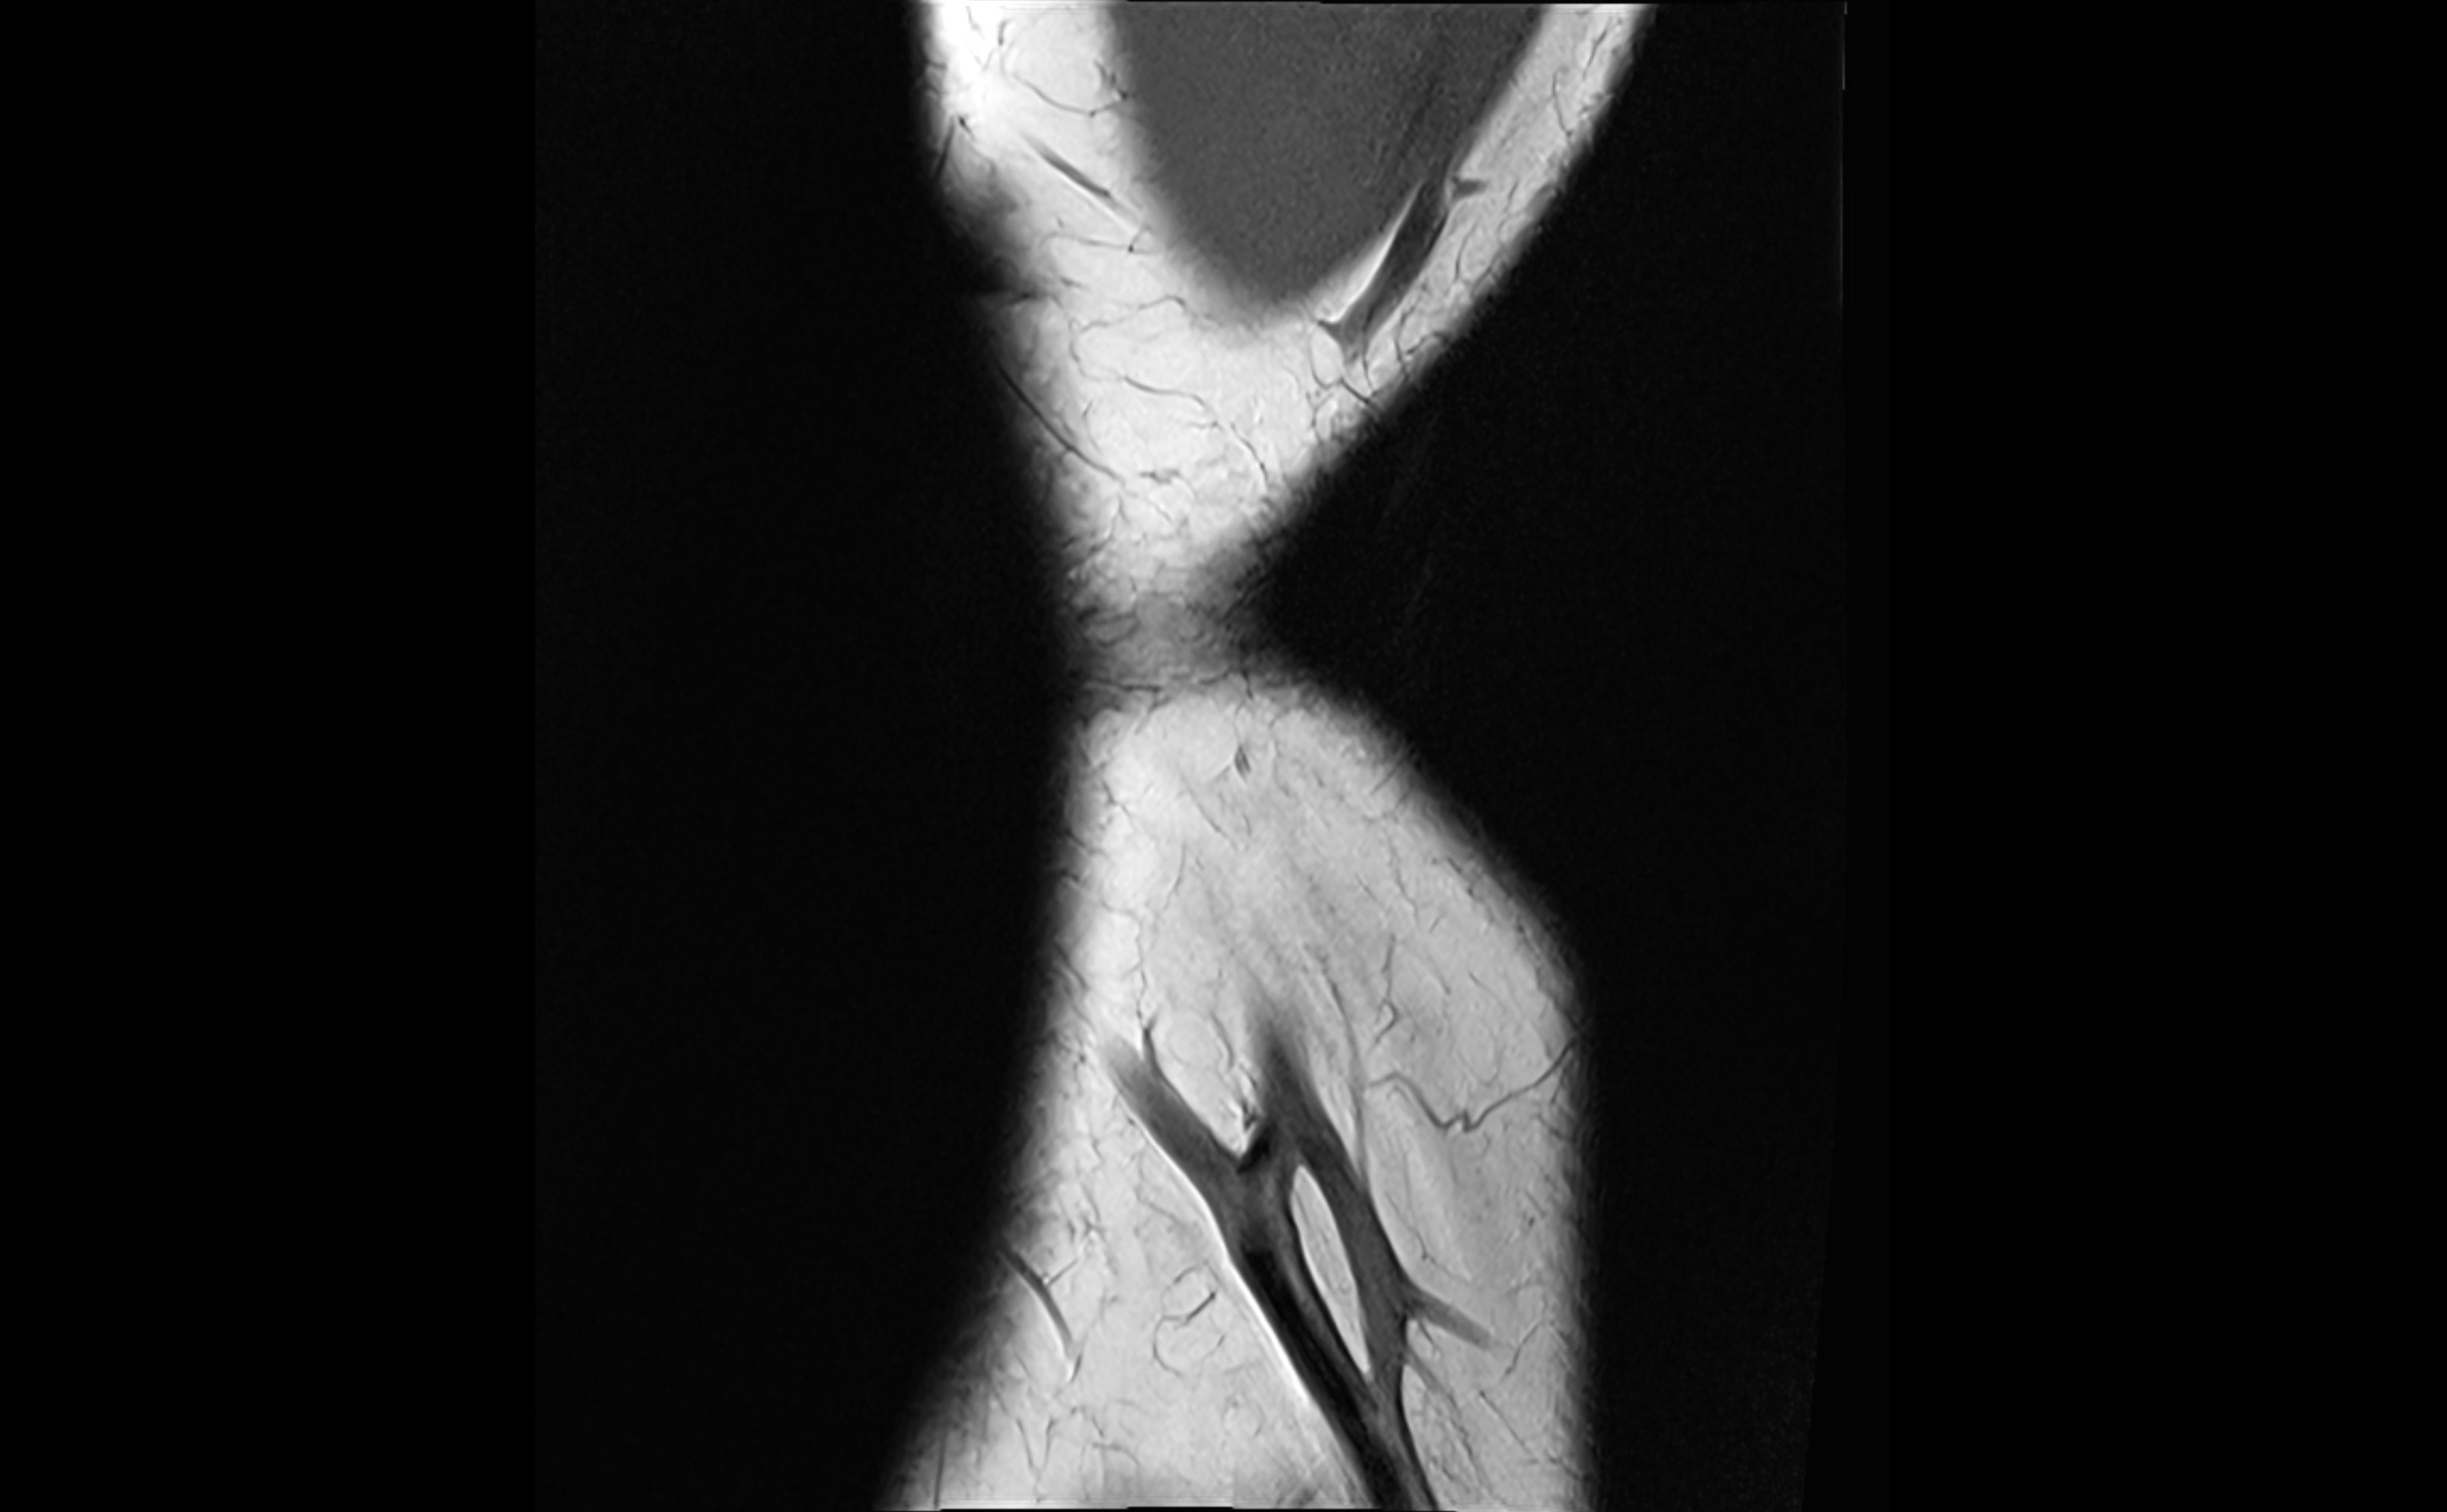

MRI Appearance

T1-weighted images:

• Ligament: low signal intensity (dark), appearing as a continuous band around the radial head.

• Adjacent fat and marrow: bright, creating contrast with the ligament.

• Thickening or disruption indicates injury or fibrosis.

• Joint capsule and synovium seen as thin low-signal lines contiguous with ligament margins.

T2-weighted images:

• Ligament: low signal (dark) with clear delineation from joint fluid.

• Fluid or edema: bright hyperintense, separating or surrounding the ligament in partial tears.

• Complete tear: discontinuity or non-visualization of ligament fibers, often with joint effusion.

STIR:

• Normal ligament: dark band encircling radial head.

• Pathology: bright hyperintense periligamentous signal suggesting edema, sprain, or partial tear.

Proton Density Fat-Saturated (PD FS):

• Normal: dark, well-defined band outlining the radial head.

• Partial tear: irregular or bright hyperintense signal within or adjacent to ligament fibers.

• Joint effusion and reactive synovitis appear bright and are well visualized.

MRI Arthrogram Appearance

• Contrast outlines the proximal radioulnar joint and radial head recess.

• Normal ligament appears as a dark ring surrounding the radial head, containing the injected contrast within the joint cavity.

• Partial tear: contrast extends along the ligament or beneath its fibers.

• Complete tear or subluxation: contrast extravasates around the radial head or ulna, indicating discontinuity.

• Detects capsular defects, instability, or synovial invagination with high sensitivity.

MRI images

image